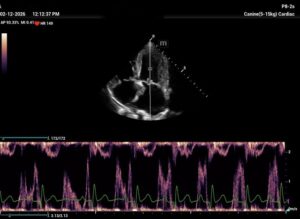

Chronic stage C MVD.TID Pimo and Lasix(high dose), ACEi and Spirono. Doing well. Recheck: Idexx GHP= CBC-NSF ,SDMA 15,BUN 14.1mmol/L, Creat 79umol/L. US: Cornell Indx LVd=1.46(prev2.1), LV septal flattening with diastolic dip,LAAO=2.47,Evel1.45m/s, TVregPG-68mmHg,HV distension-mod ascites.LV and LA underloading via diuretics and PHT (mild PHT past).PHT more pre vs post cap based on small LVsize? Consider Sildenafil/L Arg.Concerned about developing L CHF.Is CHF less likely adding PDE5i with MVD/PHT in underloaded LV than same scenario with vol overloaded LV at similar staging. MVPG=120.3mmHg

Thanks. Not sure if any sig. MV stenosis?? My experience limited.3 PWD from diff times. Ls7 vid. is from 2024,initially thinking reverse remodelling where the lasix lowering preload and Pimo is decreasing LV size via decreased resist/increase cxn while LA no change because it’s a chronic filled remodeled saggy bag receiving Regurge volume??